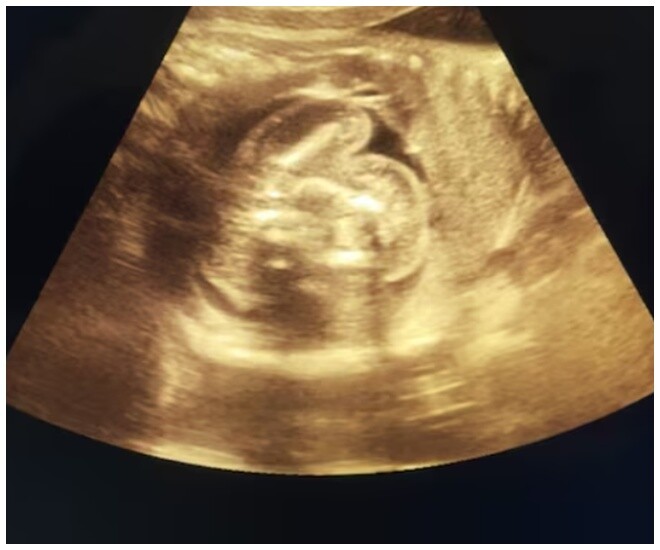

Bác sĩ phát hiện có một bào thai khác trong dạ dày của thai nhi trong bụng mẹ bầu này thông qua quá trình siêu âm. Bác sĩ sản phụ khoa tại bệnh viện, Tiến sĩ Prasad Agarwal nhớ lại: "Lúc đầu tôi rất ngạc nhiên và sau đó cẩn thận xem lại các hình ảnh. Về sau, tôi phát hiện đây thực sự là trường hợp thai trong thai hiếm gặp".

Dị tật bẩm sinh hiếm gặp này chỉ được ghi nhận ở khoảng 200 trường hợp trên toàn thế giới, với riêng Ấn Độ chỉ có 15-20 trường hợp được báo cáo ở đây. Người phụ nữ này đang ở tháng thứ 9 của thai kỳ và dị tật này không được phát hiện trong các lần siêu âm trước đó do quá hiếm gặp và khó lường.

“Điều này đã bị bỏ sót trong lần siêu âm trước vì đây là tình trạng rất hiếm gặp và không ai có thể tưởng tượng được rằng tình trạng như vậy có thể tồn tại. Vì vậy, tôi đã thực hiện một nghiên cứu chi tiết từ một vài bác sĩ và xác nhận điều đó”, Tiến sĩ Agarwal cho biết thêm.